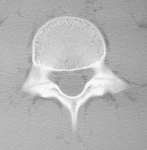

Tsukada and Colleagues present an interesting case-control study of the effect of low-intensity pulsed ultrasound (LIPUS) for early-stage lumbar spondylolysis amongst a cohort of 82 active sports participants aged between 10-18 years old, with the vast majority of these subjects playing baseball. Time required for return to previous sports activities with standard conservative treatment (including thoracolumbar bracing, activity modification and therapeutic exercises) were compared with a similar group also receiving LIPUS treatment. Amongst this cohort, median time for return to previous sports activities for the conservative treatment plus LIPUS group was 61 days, compared with 167 days for the conservative tretatment-alone group. The authors suggest that LIPUS combined with conservative treatment may be a useful therapy for shortening return to sport times.

Recently published “On Line first” in CJSM is research coming from a Japanese center renowned for its work in this area: Low-intensity Pulsed Ultrasound (LIPUS)for Early-stage Lumbar Spondylolysis in Young Athletes.